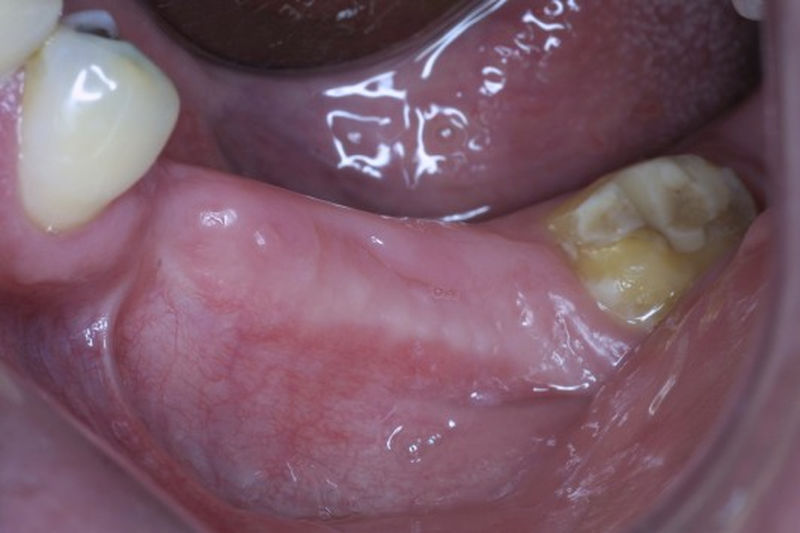

Proceso fundamental y exhaustivo que realiza el odontólogo para identificar la condición de la cavidad oral e identificar tanto zonas que esten sanas como aquellas que no lo son y buscar la causa de cualquier enfermedad o anomalía en la cavidad oral. No se limita a buscar caries, sino que ofrece una evaluación integral que sirve de base para diseñar un plan de tratamiento adecuado, efectivo y personalizado.

Disciplina fundamental de la Odontología enfocada en el diagnóstico, prevención y tratamiento restaurador de las piezas dentales que han sufrido daños. Su objetivo principal es devolver al diente su equilibrio biológico, funcional y estético cuando su integridad ha sido alterada. Resinas directas, incrustaciones, coronas.

Implante fracasado, extracción, carillas, coronas y prótesis fija.